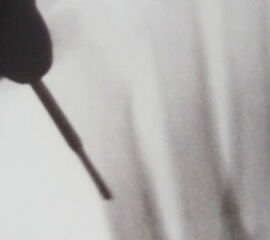

Zunächst erfolgt eine streckseitige 3 mm Inzision zwischen dem Metatarsale 4 und Metatarsale 5-Kopf (Abb. 13). Dann wird das Weichteilgewebe streng knochennah abgehoben. Mit dem Raspatorium oder einem kleinen gebogenen Klemmchen erfolgt die Tunnelierung des Raumes unter der Strecksehne wiederum streng knochennah. Von hier aus wird die kurze 2 mm Shannon Fräse eingeführt. Über diesen Zugang kann bei Bedarf auch die Exostosenabtragung durchgeführt werden. Anschließend erfolgt die Osteotomie des distalen Metatarsale 5 Schaftes (Abb. 14). Die Osteotomieebene liegt in einem 40 Grad Winkel von distal dorsal nach proximal plantar (Abb. 15). Unter Bildverstärker-Kontrolle erfolgt die korrekte Lagebestimmung der Fräse und der Osteotomie (Abb. 16). Der Drehpunkt der Fräse liegt immer in der Ebene der Hautinzision. Um keine Hautverbrennungen zu riskieren, ist das Hebeln mit der Fräse unbedingt zu vermeiden. Der Metatarsale 5-Kopf wird unter manuellem Zug an der Kleinzehe nach medial verschoben. Meist rutscht der Metatarsale 5-Kopf von selbst in die gewünschte Position (Abb. 17). Es ist extrem wichtig, dass die Osteotomieebene streng 90 Grad zur Schaftachse liegt, da es bei einer Schrägosteotomie sekundär zur Dislokation des kopftragenden Fragmentes kommen kann (Abb. 18).

Im Folgenden wird die Osteotomie aus Sicht des Rechtshänders für den rechten Fuß dargestellt: